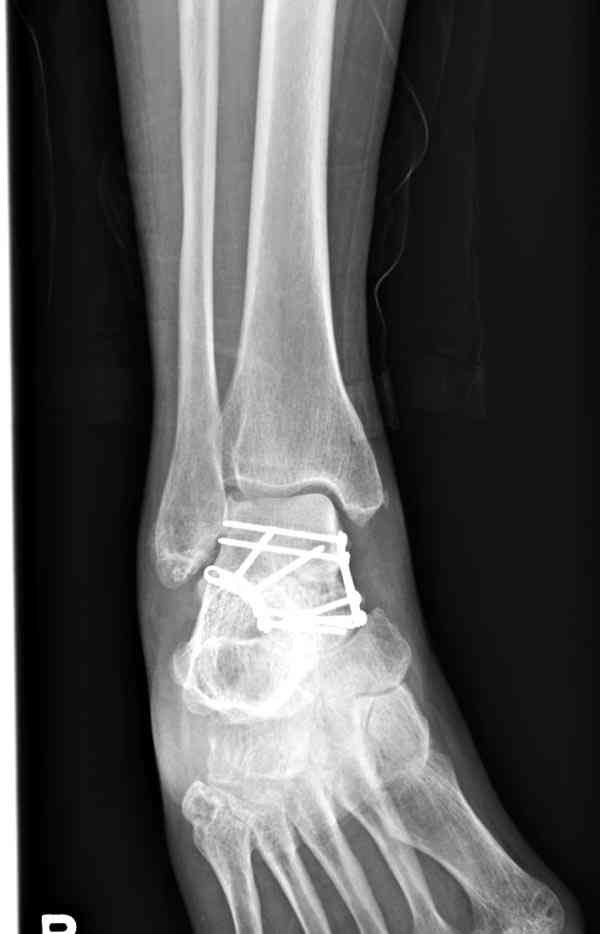

В Вашей ситуации мы произвели открытую репозицию и фиксацию металлоконструкциями. Все зажило первично, посттравматического дефартроза избежать не удалось. Пациент от артродезирующих операций в отдаленном периоде отказался.

Пациент отказался от артродезирующих операций потому что его устривает качество жизни или были какие-то другие причины (в итоге таран выглядит жутковато)